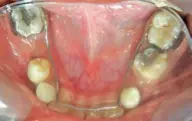

Periode gigi sulung merupakan tahap penting dalam perkembangan gigi dan rahang anak. Gigi sulung berperan menjaga ruang untuk erupsi gigi permanen, membantu fungsi pengunyahan, bicara, dan estetik. Kerusakan pada gigi sulung, seperti karies yang luas dan tidak dapat dirawat, dapat menyebabkan gigi harus dicabut sebelum waktunya, yang dikenal sebagai premature loss.

Kehilangan gigi sulung secara prematur dapat menimbulkan berbagai dampak, antara lain pergeseran gigi tetangga ke arah mesial atau distal (mesial drifting) maupun ke arah vertikal (ekstrusi). Pergeseran ini menyebabkan berkurangnya lebar lengkung rahang, gangguan perkembangan dentoalveolar, gangguan erupsi gigi permanen, ketidakseimbangan hubungan rahang, serta gangguan fungsi sistem stomatognatik. Jika tidak segera ditangani, kondisi ini dapat berujung pada terjadinya maloklusi yang dapat menyebabkan wajah anak tidak estetik.